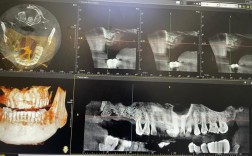

通常会引进一些先进的口腔设备,如CBCT(锥形束CT)、口内扫描仪、数字化种植导板设计制作系统等,有助于提高种植的精准度和效率。

(图片来源网络,侵删)